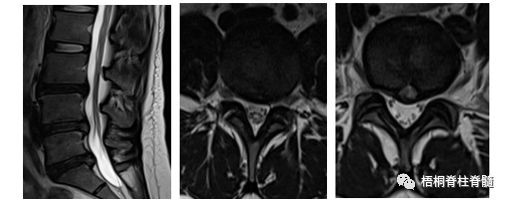

③MRI:能够清楚地显示髓核及纤维环发生脱水变化,主要表现为T2像椎间盘后缘高强化影;轴位像有时可见纤维环的裂隙。

患者女性,27岁。主诉:反复腰痛半年,加重伴活动受限4天。现病史:半年前劳累后出现腰部疼痛,经保守治疗后症状改善;后症状反复发作,保守治疗效果欠佳。4天前劳累后腰部疼痛症状再次加重,伴腰部活动明显受限,经保守治疗无效,经内镜治疗后患者症明显缓解。术前影像学资料:

男性患者,31岁。主诉:腰部疼痛10年,加重伴活动受限17天。现病史:10年前劳累后出现腰部疼痛,经保守治疗后症状缓解;后症状多次因劳累后反复出现,保守治疗效果时好时坏。17天前,患者再次因劳累后腰部疼痛加重,伴有腰部活动受限,常规保守治疗无效,内镜手术治疗后症状缓解。术前影像学资料。